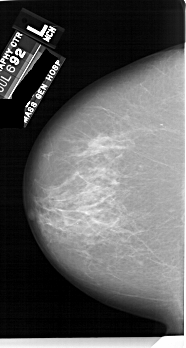

A_1749_1.LEFT_MLO

LEFT_MLO LINES 6871 PIXELS_PER_LINE 4126 BITS_PER_PIXEL 12 RESOLUTION 43.5 NON_OVERLAY